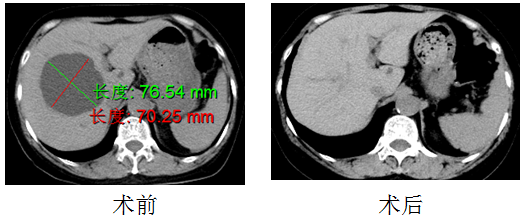

临床真实案例:

张大娘(化名),因右上腹疼痛于我院门诊体检发现肝脏多发囊肿(右叶囊肿最大截面76.54mm*70.25mm)就诊于我科,我科在排除禁忌症后,予以行肝囊肿穿刺抽液+硬化术,术后半年复查囊肿完全消失。